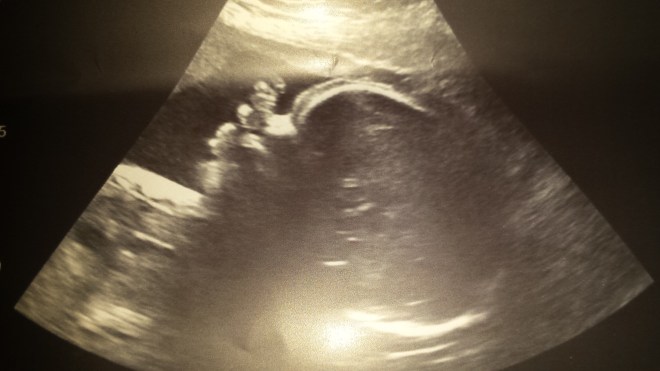

After school Madison headed to Nana’s for the afternoon. After lunch she played with her new Christmas puzzle, her baby and practiced finding her letters on the keyboard. When Mommy and Daddy picked her up after their appointment, Madison saw new pictures of her baby brother. Madison was very excited to show Nana and Mommy and Daddy were happy to report that baby #2 is doing great and is 30 weeks today!